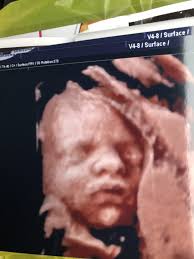

12 Weeks 1 Day Ultrasound Video Dailymotion

12 Weeks 1 Day Ultrasound Video Dailymotion from s1.dmcdn.net